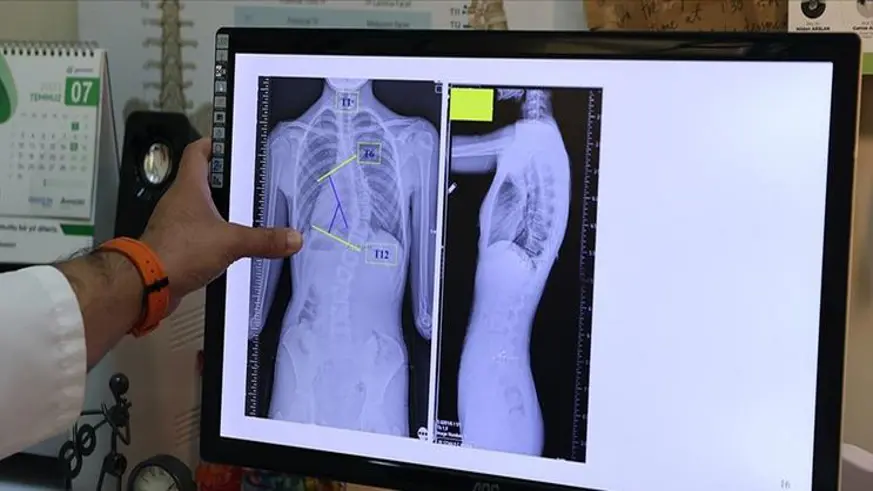

Tablet, bilgisayar ve akıllı telefonlar nedeniyle çocuklarda boyun ve bel rahatsızlıkları başta olmak üzere çok sayıda rahatsızlığın ciddi biçimde artış gösterdiği belirtiliyor. Bu aletler, yoğun biçimde kullanım nedeniyle gelişme çağındaki çocukların omurgalarında ciddi hasara yol açıyor.

Konuyla ilgili Beyin, Sinir ve Omurilik Cerrahisi Uzmanı Prof. Dr. Orhan Şen, İhlas Haber Ajansı’na açıklamalarda bulundu. Prof. Dr. Şen, "Omurga pozisyonunu korumanın yolları çocukluktan başlıyor. Bunun da asıl rolü ebeveynlerde. Çocukları mutlaka ebeveynler küçük yaştan itibaren spora yönlendirmeliler. Çocuklar maalesef hep masa başındalar. Bilgisayar, cep telefonu ve tabletle zamanlarını geçiriyorlar. Kısacası sıfır hareket ediyorlar. Ebeveynler ısrarla çocuklarını mutlaka yüzme veya farkı branşlara yönlendirmeliler" dedi.